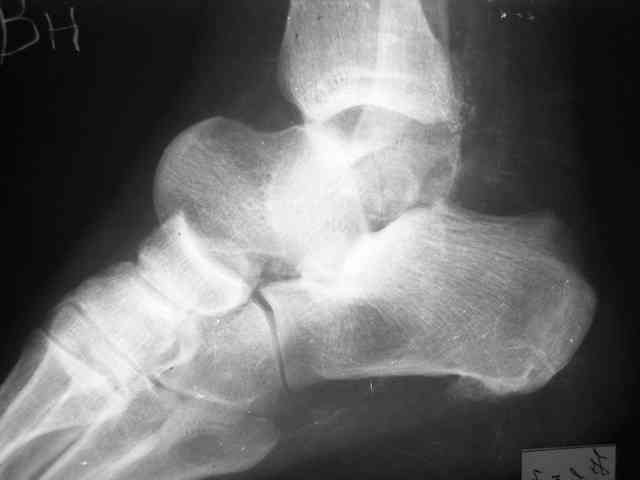

Уважаемый Александр! Как обещал представляю Р-граммы и операционные фото.

Последний снимок

Мнение по поводу тарана? АН есть?

Типичная картина некроза.